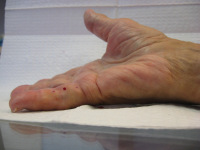

Despite this, recurrence is likely due to

early age of onset and ectopic disease:

unusual Ledderhose with toe nodules (left);

unusual knuckle pads at the DIP joints (right)